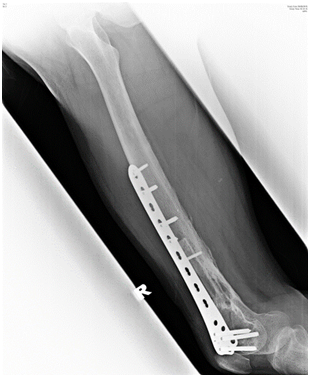

Postoperative radiograph showed acceptable fracture alignment with autogenous fibular graft inside the medullary canal (Figures 2A & 2B).

The patient was allowed active mobilization of the knee joint after surgery but weight bearing on the injured limb was strictly not allowed. The patient was allowed partial weight bear and full weight bear at 4 and 6 months respectively. The fracture achieved radiological union at 6 months after internal fixation and bone grafting (Figure 3A & 3B). Patient was able to ambulate independently without aid. Right lower limb however was shorter by 2cm but patient did not have any functional complain and this can be equalized with a shoe lift. Right thigh muscles were atrophic. Passive range of motion of the right knee was 0 to 130 degrees while active range of motion was 10 to 120 degrees. Ankle joint was stable. Fibular graft donor site healed with no complication.

Figure 3a Figure 3A(Right) Radiograph of the right femur, AP view, six months after surgery showing fracture site union with incorporation of the fibula graft.

Figure 3b (Left) Radiograph of the right femur, lateral view, six months after surgery showing fracture site union with incorporation of the fibula graft